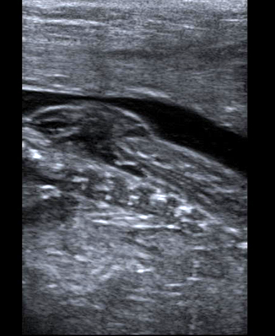

Speciman of metastatic lymph node after blue dye injection.

Intra-operative ultrasound has also emerged as an important tool:

- In accurately staging metastatic cancer such as in liver or colorectal disease,

- For intra-operative injections of “blue dye” into small metastatic lymph nodes (see image above),